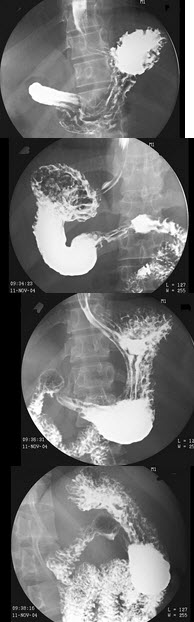

5、单项选择题 头颅凹陷性骨折,应首选哪种投照体位()

女,53岁,常感中上腹不适,结合图像,最可能的诊断为()

女,50岁,血便10余年,加重1年(连续出血),近2月大便时肛门常滴鲜血,量较多,X线检查如图,最可能的诊断是()